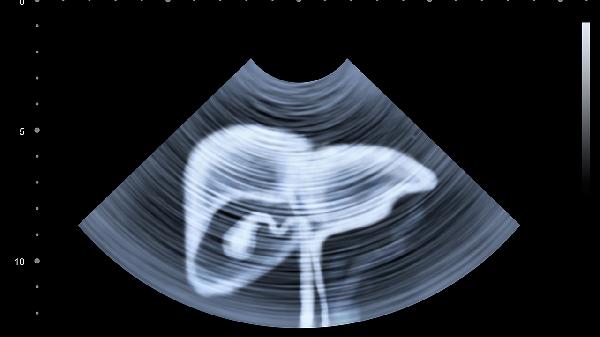

肝脏低密度结节是指肝脏组织出现密度较低的纤维化,考虑是肝结节性再生性增生、肝硬化、肝腺瘤等原因引起的。

1、肝结节性再生性增生:肝结节性再生性增生可能是由于系统性红斑狼疮、干燥综合症、骨髓纤维化等全身系统性疾病引起的。患病后肝脏会发生实质蔓延性再生小结节、轻微肝纤维化。做影像检查时可发现肝脏低密度结节。早期肝结节性再生性增生,可服用扶正化瘀胶囊等药物治疗。如果出现了门静脉高压、肝衰竭,则需要通过手术治疗。

2、肝硬化:肝硬化可能是由于长期服用某种药物、遗传、病毒性肝炎等原因引起的,会使肝组织发生弥漫纤维化或者再生结节。做CT检测时出现肝脏低密度结节。早期肝硬化可以服用恩替卡韦、多烯磷脂酰胆碱胶囊等药物治疗。如果肝硬化发展为终末期,需要通过肝移植手术治疗。

3、肝腺瘤:肝腺瘤可能是由于口服避孕药导致体内激素水平异常引发的,会影响肝细胞的活性以及功能。做影像学CT检查时结果会显示肝脏低密度结节,需要做进一步做彩超等检查。确诊后通过手术切除,常见手术有肿瘤切除术、肝叶切除术等。